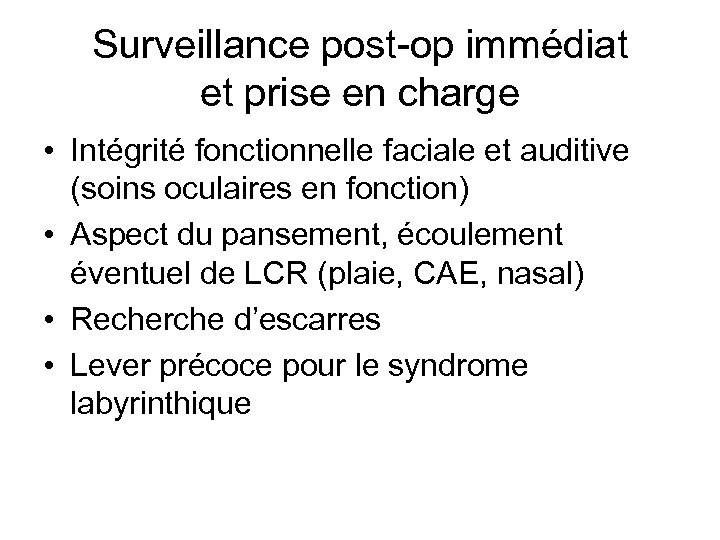

Surveillance post-op immédiat et prise en charge • Intégrité fonctionnelle faciale et auditive (soins oculaires en fonction) • Aspect du pansement, écoulement éventuel de LCR (plaie, CAE, nasal) • Recherche d’escarres • Lever précoce pour le syndrome labyrinthique

Surveillance post-op immédiat et prise en charge • Intégrité fonctionnelle faciale et auditive (soins oculaires en fonction) • Aspect du pansement, écoulement éventuel de LCR (plaie, CAE, nasal) • Recherche d’escarres • Lever précoce pour le syndrome labyrinthique